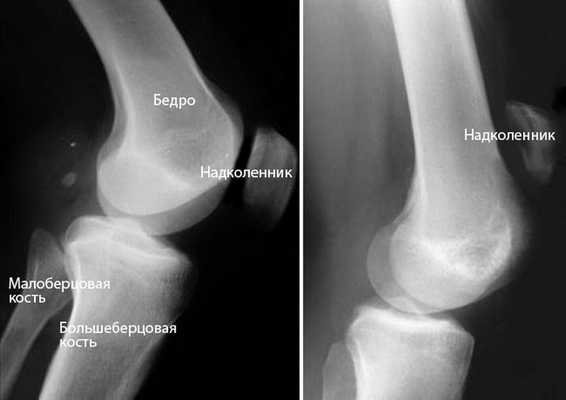

Рентгенография. При разрыве сухожилия надколенника последний смещается вверх, что очень хорошо видно на рентгенограмме в боковой проекции. Для подтверждения диагноза полного разрыва этой рентгенограммы обычно бывает достаточно.

(Слева) Нормальное положение надколенника на рентгенограмме в боковой проекции. (Справа) Смещение сухожилия надколенника вверх при разрыве его сухожилия.